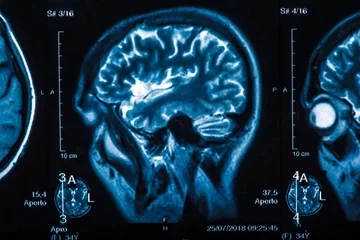

Intracranial aneurysms (ICAs) are an increasingly common finding, both from incidental discovery on imaging studies and on autopsy; it is estimated that anywhere from 1-6% of the American population will develop this problem. Unfortunately, while our ability to detect ICAs has grown, our fundamental understanding of this disease entity remains lacking and significant debate continues in regards to its treatment. Given the high degree of mortality and comorbidity associated with ruptured intracranial aneurysms, it is imperative that new insights and approaches be developed to inform medical decision making involving ICAs.